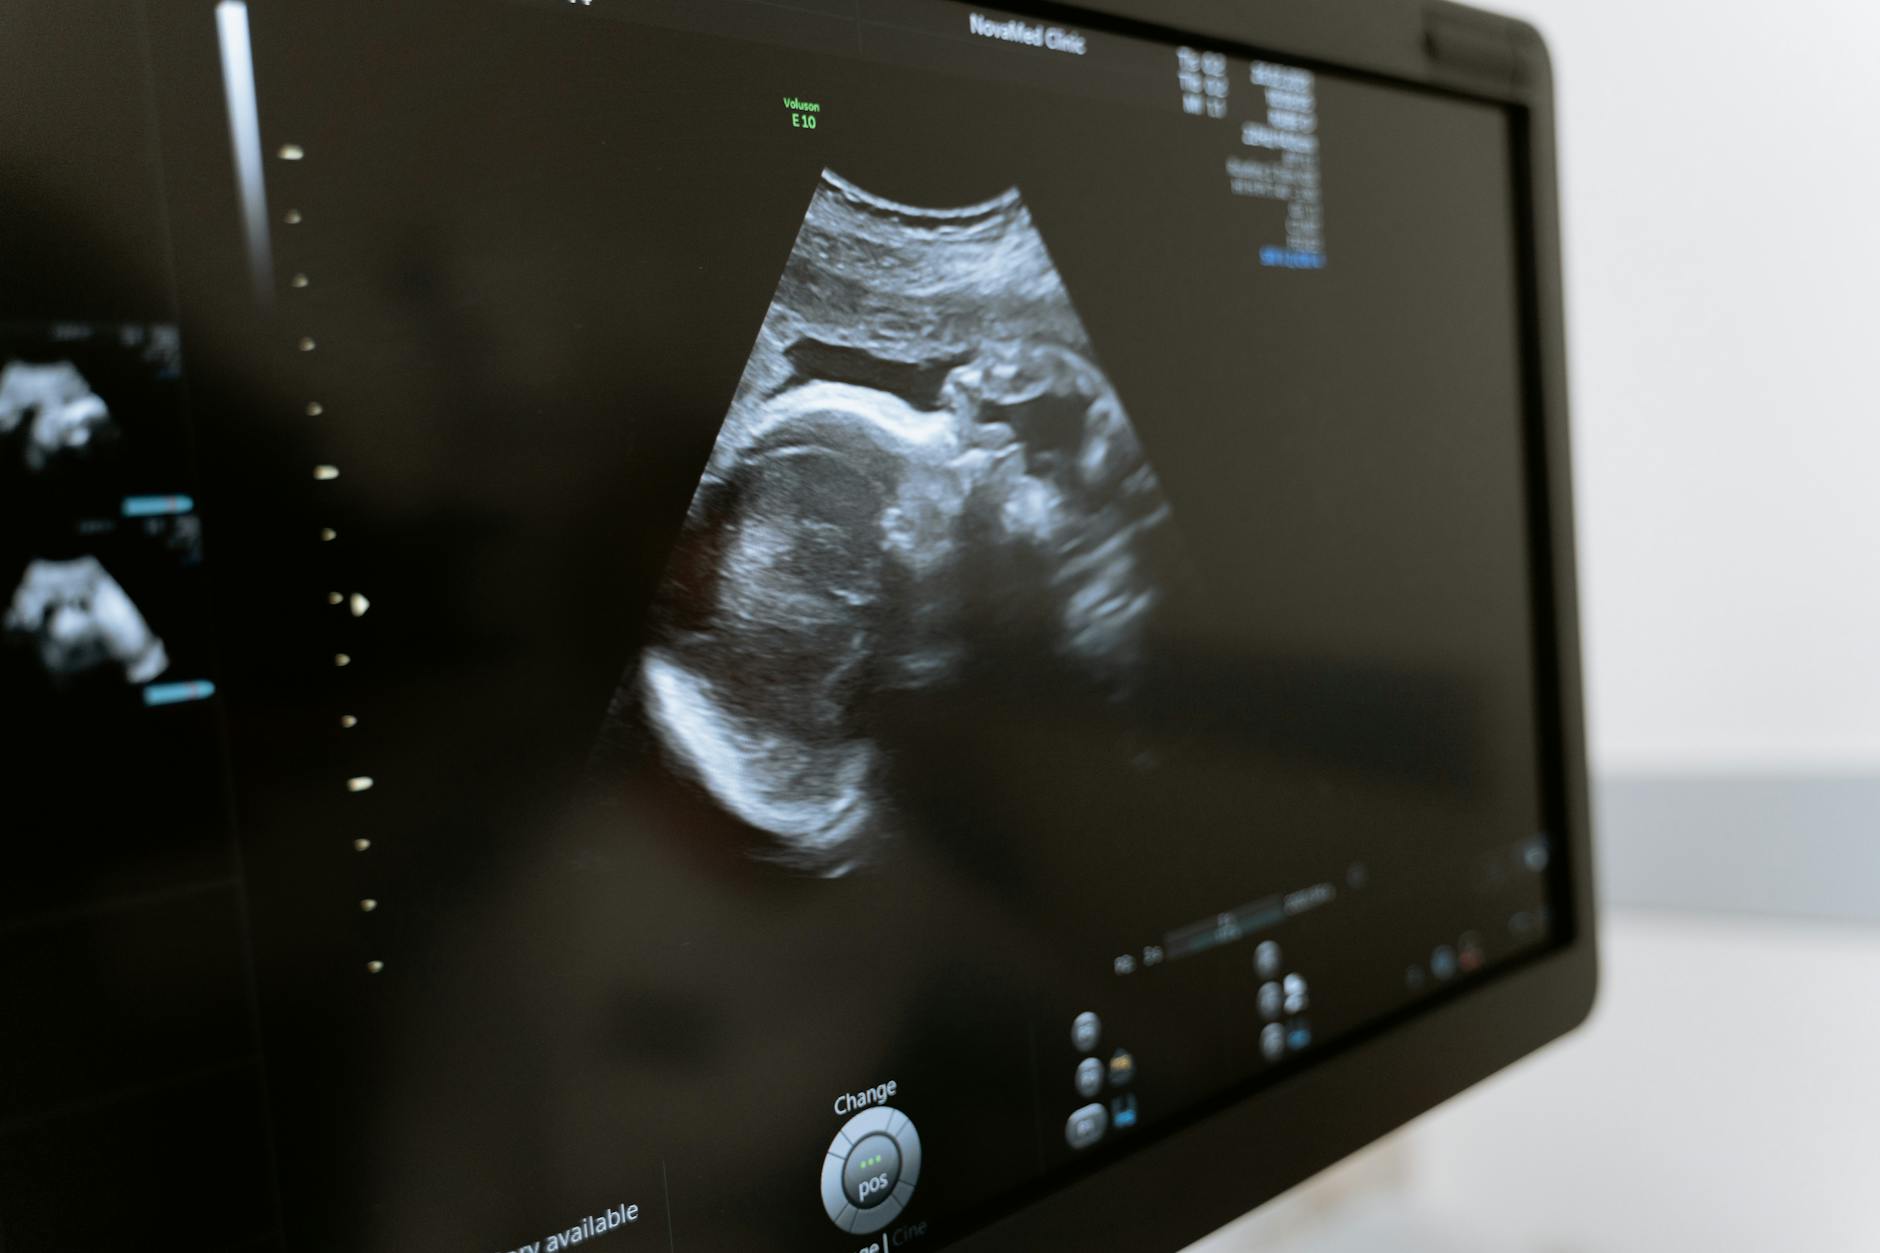

Gynaecologie, verloskunde en echografie

Foto door MART PRODUCTION op

Pexels.com